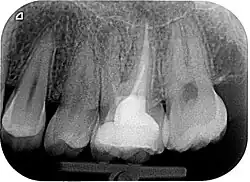

Zur Beurteilung des Erfolges einer Wurzelkanalbehandlung werden klinische Beschwerden, wie Schmerzen, Schwellungen oder Fistelgänge sowie der röntgenologische Befund herangezogen. Oft sind trotz endodontischer Infektion keine klinischen Beschwerden vorhanden, weshalb gerade die röntgenologische Kontrolle Hauptkriterium für die Beurteilung ist.[10] Neben der vorhandenen Wurzelfüllung und Veränderungen in der Wurzelphysiognomie (Resorptionen) wird vor allem der Zustand des periapikalen Gewebes begutachtet und auf das Vorhandensein einer Parodontitis apikalis oder einer radikulären Zyste geprüft.

- Bei Zähnen mit unzureichender Wurzelfüllung mit röntgenologischem Befund einer entstehenden oder verbliebenen Parodontitis apikalis (Entzündung des Gewebes, das die Zahnwurzel umgibt) und/oder Symptomen (Schmerzen, Beschwerden).

- Wurzelkanalbehandelte Zähne mit röntgenologischen Symptomen einer persistierenden oder neu entstandenen, endodontisch bedingten Parodontitis apicalis.

- Wurzelkanalbehandelte Zähne mit röntgenologisch oder klinisch insuffizienter Wurzelkanalfüllung (z. B. mangelhafte Homogenität der Füllung, nicht behandelte Wurzelkanäle, nicht gefüllte Areale des endodontischen Systems, fragwürdiges und nicht mehr indiziertes Füllmaterial etc.) ohne klinische oder röntgenologische Anzeichen einer Parodontitis apicalis.

Die Erfolgsrate der Wurzelkanalrevisionsbehandlung hängen sehr stark vom Ausgangsbefund ab. Vor allem ob eine periapikalen Läsion bei Behandlungsbeginn bestand, ist entscheidend für die Prognose. Friedman und Mor zeigten, dass bei Erstbehandlungen sowie Revisionsbehandlungen ohne eine Entzündung an der Wurzelspitze die Erfolgsraten zwischen 92 % und 98 % in der 10 Jahreskontrolle erreicht werden. Bei Vorhandensein einer Parodontitis apikalis sinken die Heilungschancen auf Werte zwischen 74 % und 86 % (23) Im Mittel werden in der Literatur Erfolgsquoten von Revisionsbehandlungen von 60 % bis 80 % angegeben.[1]